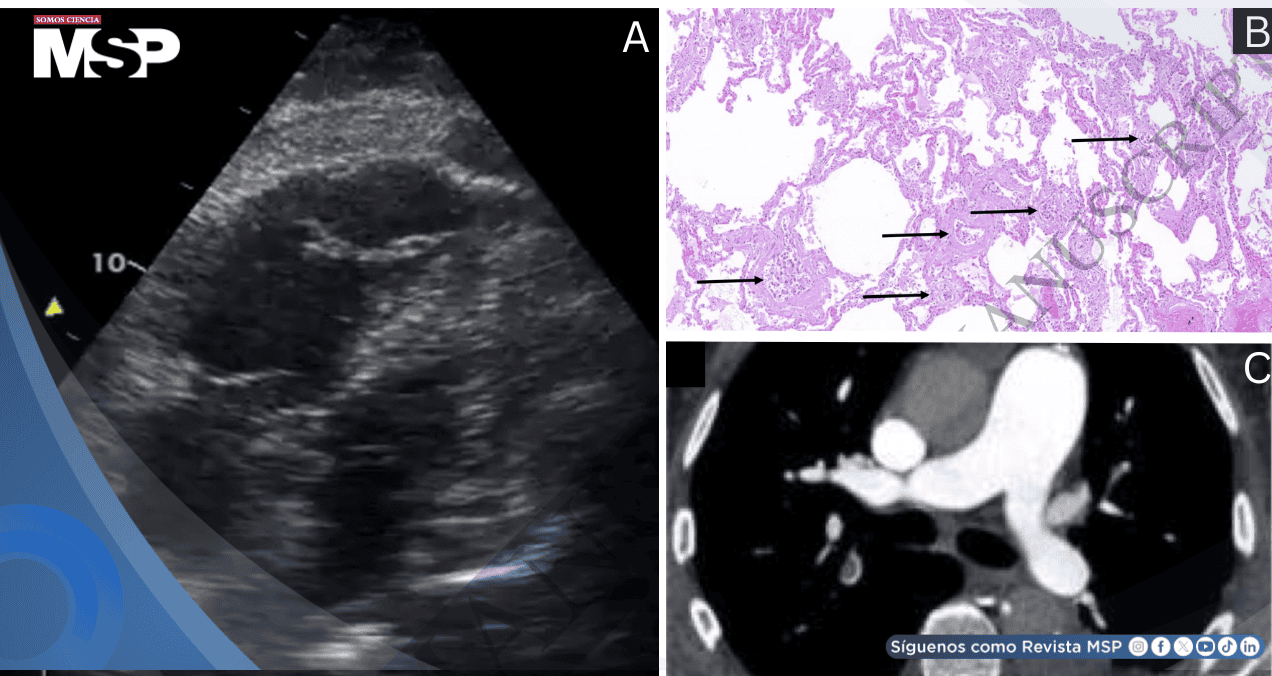

La ecocardiografía urgente reveló ventrículo derecho dilatado con sobrecarga de presión y signo de McConnell. La angiotomografía torácica descartó tromboembolismo pulmonar, y la ausencia de dolor torácico con función ventricular izquierda normal hizo improbable la obstrucción coronaria post-TAVI.

La autopsia clínica reveló un TAVI correctamente posicionado con arterias coronarias permeables. Se diagnosticó carcinoma urotelial invasivo pT2b pM1b con trombosis microangiopática tumoral en la vasculatura pulmonar y hepática.

La causa de muerte se atribuyó a shock obstructivo por sobrecarga aguda del ventrículo derecho secundaria a microangiopatía trombótica tumoral pulmonar.

La microangiopatía trombótica tumoral pulmonar (PTTM), según los autores, Victor García-Hernando et al., es una complicación rara pero fatal asociada a tumores sólidos avanzados, especialmente gástricos, uroteliales y ováricos. Consiste en la embolización de células tumorales hacia los lechos capilares pulmonares, hepáticos y renales, causando activación plaquetaria, microtrombos y disfunción endotelial.